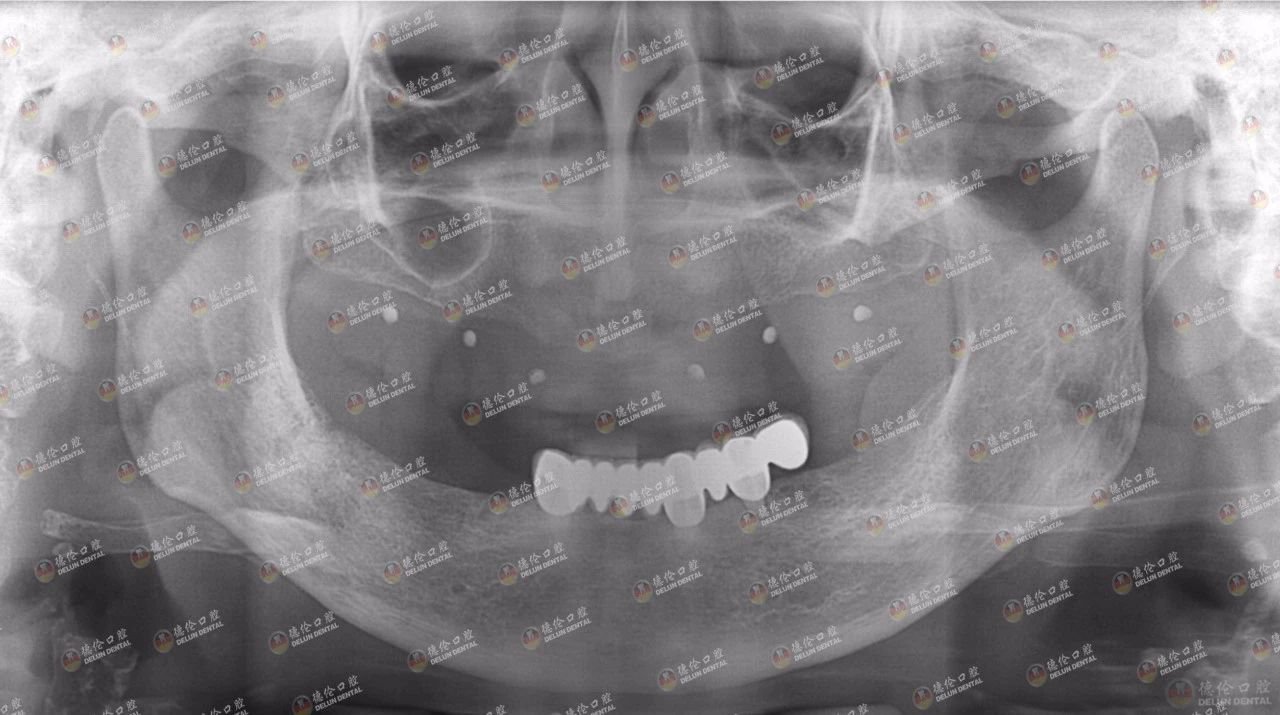

吴女士来德伦口腔诊疗时的牙片显示,只剩左下颌的种植牙,骨量不足

吴女士种植带冠后的牙片显示,种植体就位准确,受力均衡